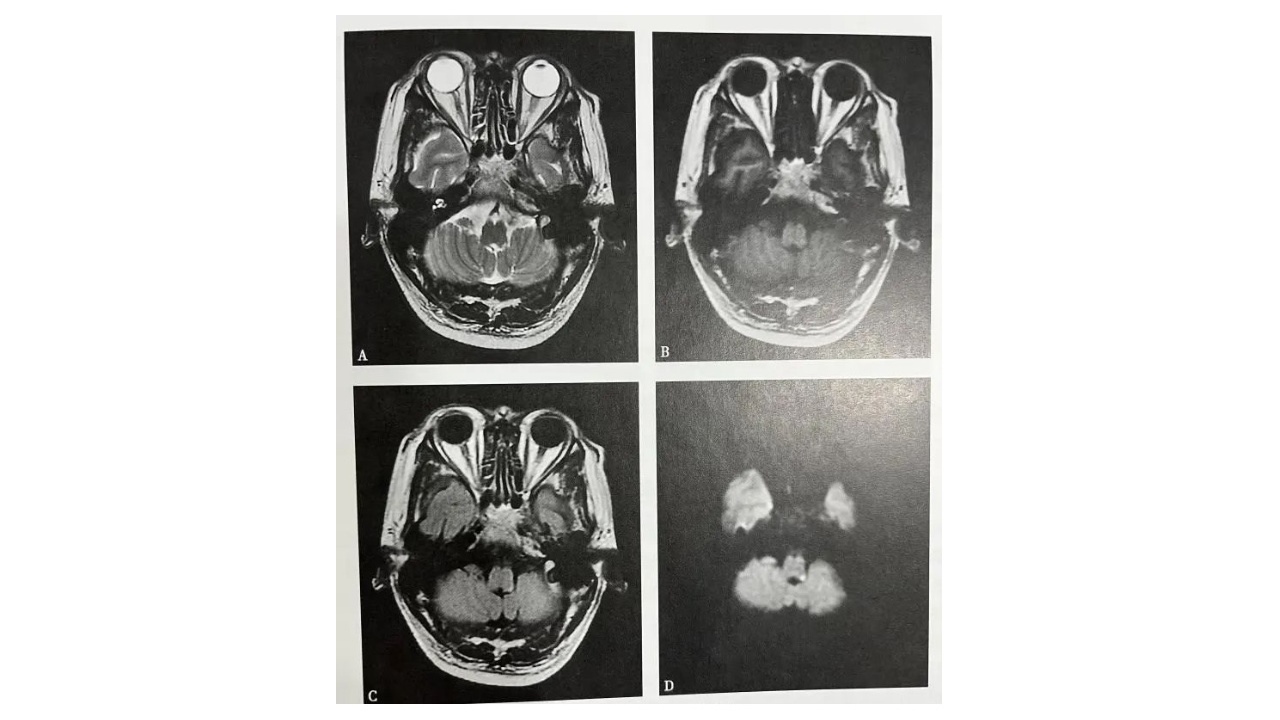

图2.延髓脑梗死

A~D(A.T2WI,B.T1WI,C.T2WI-FLAIR,D.DWD):延髓左侧背侧可见斑条状等T1略长T2信号灶,边界不清,FLAIR及DWI呈高信号灶,最大截面约8mmx2mm,边界不清